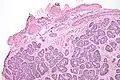

Micrograph of a Sertoli cell nodule. H&E stain.

Sertoli cell nodules are unencapsulated nodules that consist of:[2][3][4]

- cells arranged in well-formed tubules (that vaguely resemble immature Sertoli cells), with

- bland hyperchromatic oval/round nuclei that are stratified, and

- may contain eosinophilic (hyaline) blob in lumen (centre).